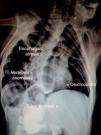

A 9-year-old boy was diagnosed with a tracheoesophageal fistula and esophageal atresia at birth, both of which were surgically repaired. At the follow-up visit with the services of Pediatrics and Gastroenterology of our hospital center, the chest and abdominal x-ray presented herein showed the presence of situs inversus, morphologic abnormalities, and vertebral fusion, as well as postsurgical changes in the esophageal repair, all of which are characteristic findings of the VACTERL association (Fig. 1).

Some authors prefer the term «association» rather than «syndrome» due to the fact that the complications are not pathophysiologically related and because there is no specific etiology, even though the alterations occur in organs derived from the mesoderm and the pathology presents more frequently in the children of diabetic mothers. The VACTERL association (V: Vertebral anomalies, A: Anal atresia, C: Cardiovascular abnormalities, TE: Tracheoesophageal fistula, R: Renal anomalies, L: Limb defects) is defined by the presence of at least 3 of the malformations just mentioned. Patient management is divided into 2 stages: in the first, conditions that are life-threatening, such as severe cardiac malformations, are treated surgically; and in the second, the remaining malformations continue to be under long-term control and rehabilitation (Fig. 2).